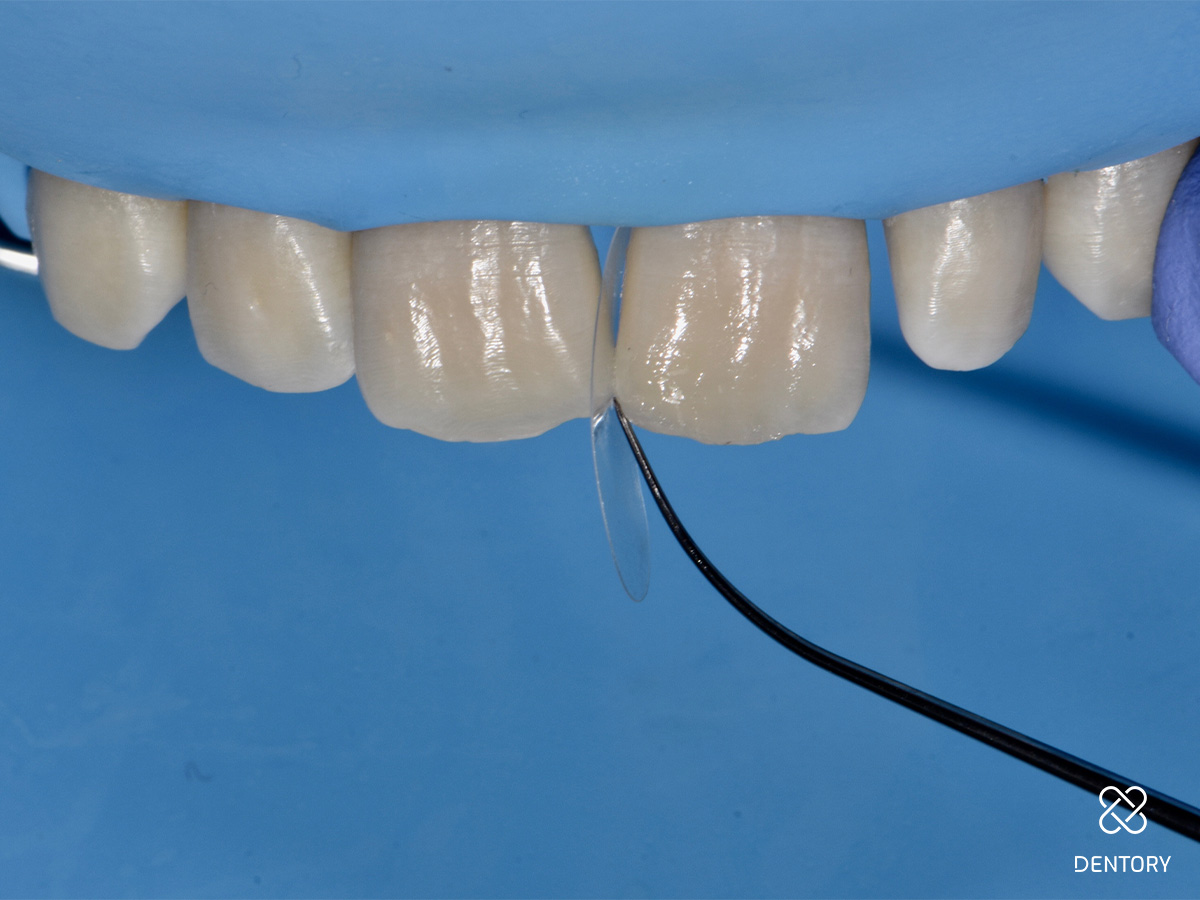

Abbildung 2

Die großzügige Isolierung der Zähne 13-23 mit Kofferdam gewährleistet ein trockenes und störungsfreies Arbeitsumfeld und bietet die Möglichkeit, sich an benachbarten Strukturen zu orientieren.